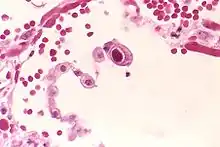

| Typical "owl eye" intranuclear inclusion indicating CMV infection of a lung pneumocyte[1] | |

- ↑ Mattes FM, McLaughlin JE, Emery VC, Clark DA, Griffiths PD (August 2000). "Histopathological detection of owl's eye inclusions is still specific for cytomegalovirus in the era of human herpesviruses 6 and 7". Journal of Clinical Pathology. 53 (8): 612–4. doi:10.1136/jcp.53.8.612. PMC 1762915. PMID 11002765.